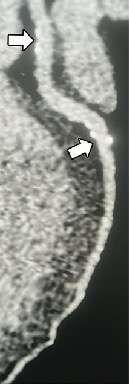

如下一名患有稳定型胸痛的 48 岁女性的图像显示,

心脏 CT 扫描(左图)显示左前降支冠状动脉近端有阻塞性狭窄(箭头),这一处左前降支冠状动脉近端的狭窄在ICA的图像(右图)被证实了。

DISCHARGE试验表明,对于因稳定型胸痛而接受检查的患者,心脏 CT是比ICA更安全的“守门员”。

且受益于心脏 CT无创的特点,心脏CT组的检查并发症有所减少。